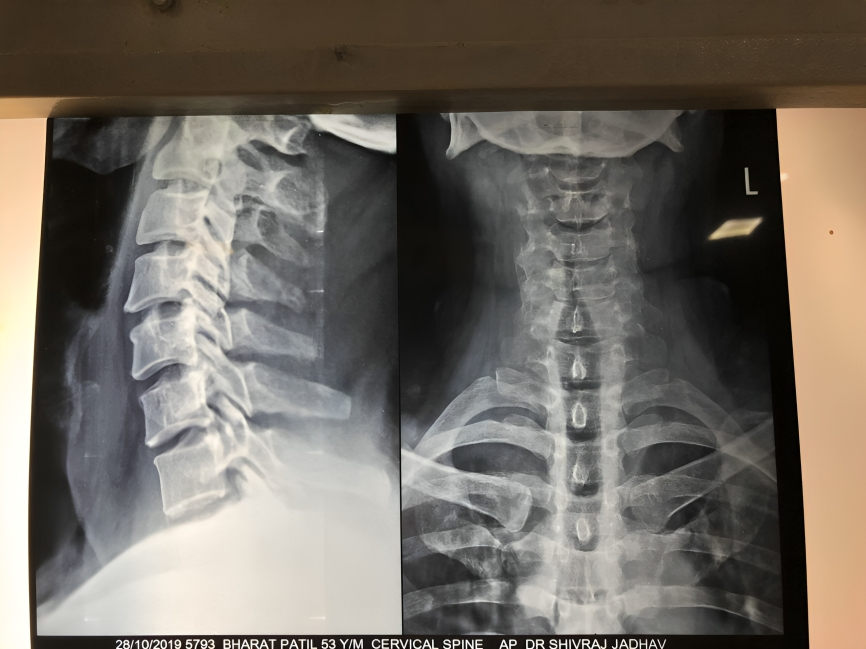

He is skilled in endoscopic evaluations, minimally invasive ENT procedures, vertigo assessment and advanced ear - nose - throat care, ensuring precise and patient-friendly treatment.